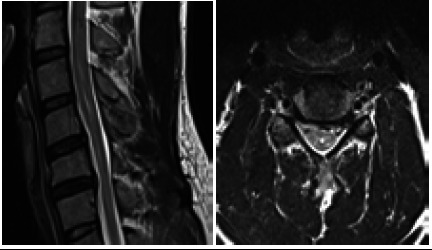

平山病是一种罕见的良性神经系统疾病,主要累及C5至T1脊髓前角,主要累及C7和C8。平山病是由于脊髓过度拉伸导致脊柱与硬脑膜之间生长不平衡,导致脊髓前部微循环紊乱,尤其是颈部屈曲时,引起单侧或很少不对称的双侧上肢无力和肌肉萎缩。这是一个21岁的男孩,他的左手和前臂虚弱了2年,在寒冷的天气和颈部弯曲时加重。颈部x线平片和颈椎MRI显示平山病的特征。

Hirayama disease is a rare benign neurological disease that affects the anterior horn of the spinal cord at C5 to T1, mainly at C7 and C8 due to imbalance growth between the vertebral column and the dura mater leading to microcirculatory disturbances in the anterior portion of the spinal cord due to overstretched cord, especially during flexion of the neck causing unilateral or rarely asymmetrically bilateral upper limb weakness and muscle wasting. It is a case of a 21-year-old boy presented with weaknesses in his left hand and forearm for 2 years which aggravates during cold weather and flexion of the neck. A plain x-ray of the neck and MRI of the cervical spine were conducted which show the features of Hirayama disease.